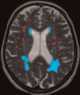

Deep white matter ischemia